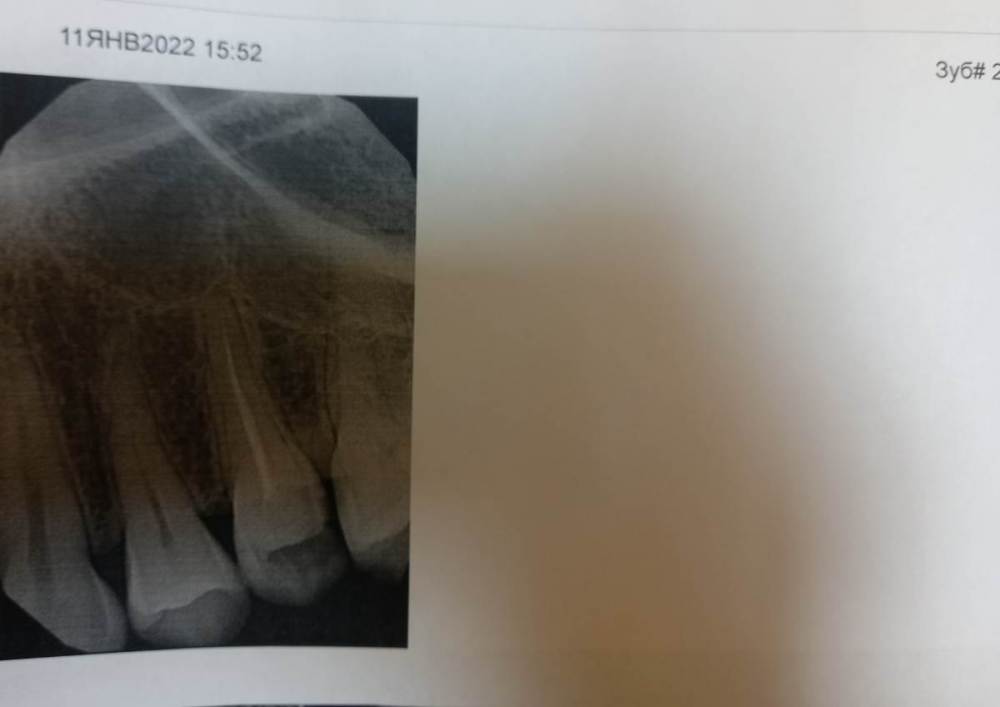

Mariaduya Опубликовано 5 июля, 2023 Поделиться Опубликовано 5 июля, 2023 (изменено) Здравствуйте. У меня сложная ситуация, боли в челюсти практически 1.5 года. Врачи не видят проблем, уже не знаю куда обратиться. Хронология. 1. В ноябре 2021 начал слегка болеть 1.6 зуб. В стоматологии мне его сразу начали депульпировать, без снимка. В ходе лечения не болел, как запломбировали каналы, постепенно появилась ноющая, постоянная боль. Я обратилась снова, сказали, что на зубе есть хроническое воспаление и ввели антибиотик туда при помощи электрофареза. Среагировал 2.5 зуб с другой стороны, и тоже начал постоянно болеть, он был депульпирован давно, но в нем развился большой кариес. 2. Мне начали их перелечивать. 1.6. не получилось пройти канал, залили резодентом, 2.5 просто переличили. 3. Боль все ещё осталась, уже в двух зубах. Врачи ничего не знают, отправили к неврологу, ЛОРУ и т.д. 4. Обошла неврологов, лоров, делала мрт, кт с контрастом головы, пазух носа, все ок. Невролог выписывает финлепсин, не помог. 5. Делала в частной клинике кт зубов, без описания, ещё не знала, что оно нужно, врач посмотрела и сказала, что видит небольшое, хроническое воспаление на 1.6 зубе и все, а так она не знает. 6. И так 1.5 года никто не знает, что со мной. Боль 1.6 и 2.5 зубы, начинают и нижние зубы болеть, уже и ухо болит. После орви болит все очень сильно, что хочется уже не просыпаться. Удалять их говорят не показаний, вдруг боль останется. Снимки в хронологии выкладываю. Есть ли на них воспаление 1.6 зуба, 2.5 зубов, есть ли них кисты свищи и все что угодно, что аномально и может вызывать боль. Может что-то с надкостницой, или суставами. Все что у меня есть - интернет, так как живу я очень далеко от нормального города и доступна только городская поликлиника, где врачи говорят, что это неврология, а невролог говорит наоборот. Сами зубы болят странно, по очереди. Если болит неделю 1.6 зуб, то 2.5 не болит и так наоборот. Вместе они не болят. Ещё странное то, что они практически симметричны друг другу по расположению. Изменено 5 июля, 2023 пользователем Mariaduya Ссылка на комментарий

Carioznik Опубликовано 5 июля, 2023 Поделиться Опубликовано 5 июля, 2023 Здравствуйте, 27 зуб надо внимательнее посмотреть, возможно там пульпит (но это неточно "бумажные " снимки малоинформативны). Скиньте лучше КТ или хотя бы ОПТГ но в электронном формате(а не фото распечатки на бумаге) Ссылка на комментарий